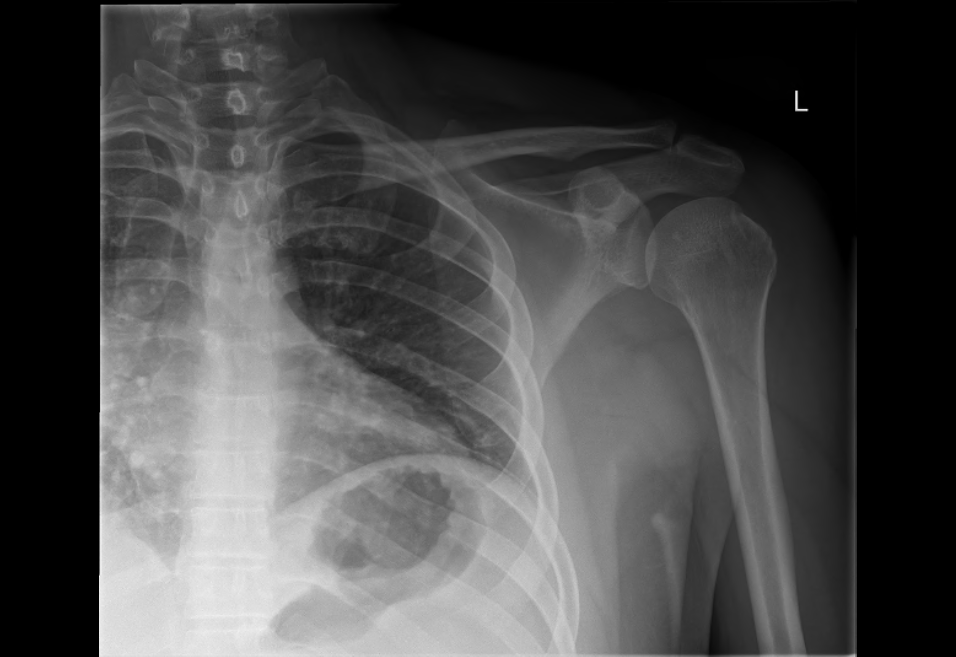

Another X-ray to confirm the situation.

Much better…..